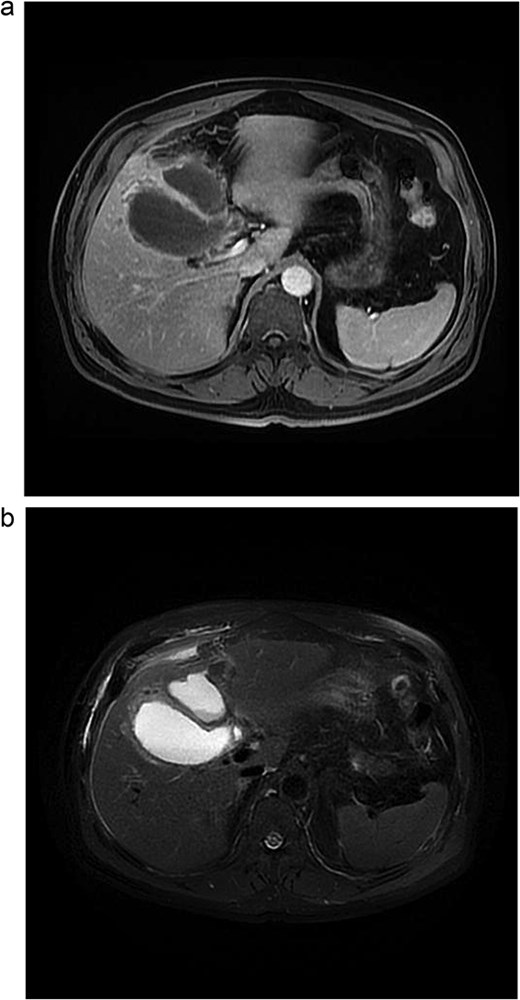

Lab tests showed leukocytosis (15.2 × 103/μl), thrombocytopenia (95.8 × 103/μl), elevated CRP (25.22 mg/dl), procalcitonin (4.49 ng/ml), and total bilirubin (3.5 mg/dl). Liver function was otherwise normal. Ultrasound revealed lithiasic cholecystitis with hydrocholecystosis. Computed tomography (CT) failed to detect duplication (Fig. 1a and b). MRCP confirmed H-type duplicated gallbladder with two independent cystic ducts and mild extrinsic compression of the extrahepatic bile duct (Mirizzi-like pattern) (Figs 2 and 3). MRI sequences (T1 LAVA-Flex and T2 PROPELLER with fat suppression) also demonstrated the duplicated gallbladder and supported the MRCP findings (Fig. 4). No choledocholithiasis was seen.

Abdominal MRI. (a) Axial 3D T1 LAVA-Flex water-only sequence, venous phase. (b) Axial T2 PROPELLER sequence with fat suppression.